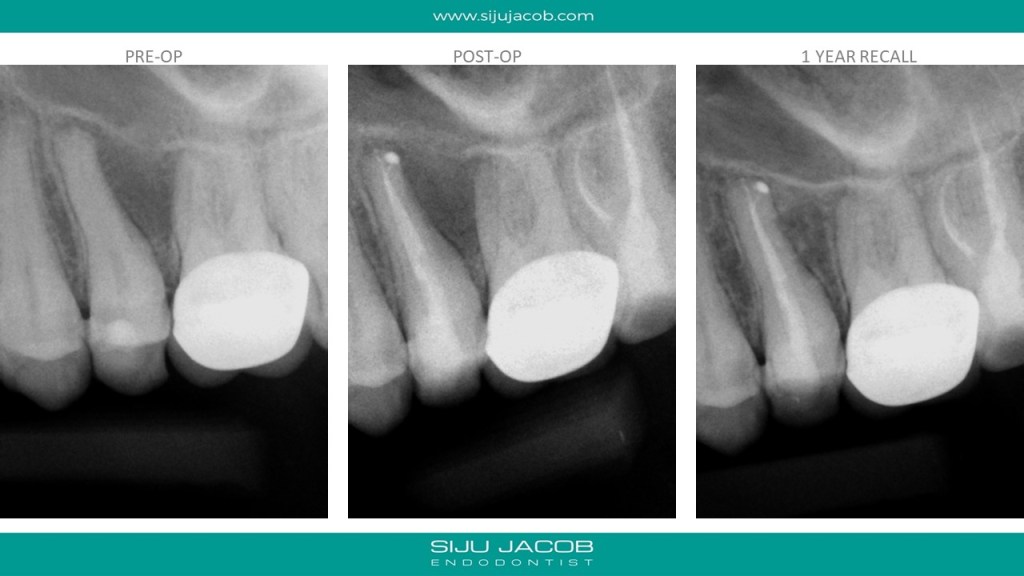

This patient presented with a lesion in between the second pre-molar and first molar. The second pre-molar tested non-vital. In the caoh radiograph taken after the first session, You can see the calcium hydroxide going through a lateral canal into the lateral lesion. I however, couldn’t get sealer into the the lateral canal during the obturation. It still healed pretty well though.